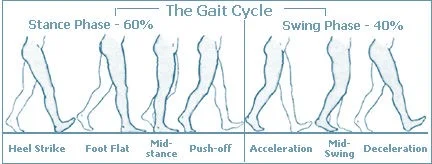

Gait Assessment

- Walking gait analysis

Special Tests: Gait Analysis

The Normal Gait Cycle

Stance phase (60%)

- Heel strike

- Foot flat - mid-stance

- Push off

Swing phase (40%)

- Acceleration

- Mid-swing

- Deceleration

Gait Patterns and Interpretation

| Gait Type | Explanation |

|---|---|

| Normal | Normal stance and swing phases |

| Antalgic | Painful to weight-bear – short stance phase |

| Lurch | Shortening – painless limping – normal stance period |

| Circumduction | Stiff hip – motion of pelvis compensates |

| High Step | Foot drop – more hip & knee flexion needed to free toes from ground |

| Tip-toe | Heel off the ground |